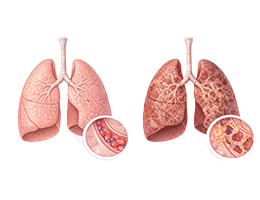

폐렴 (Pneumonia)

만성폐쇄성폐질환 (Chronic Obstructive Pulmonary Disease)

폐기종 (Emphysema)

폐섬유증 (Pulmonary Fibrosis)

특발성폐섬유증 (Idiopathic pulmonary fibrosis)